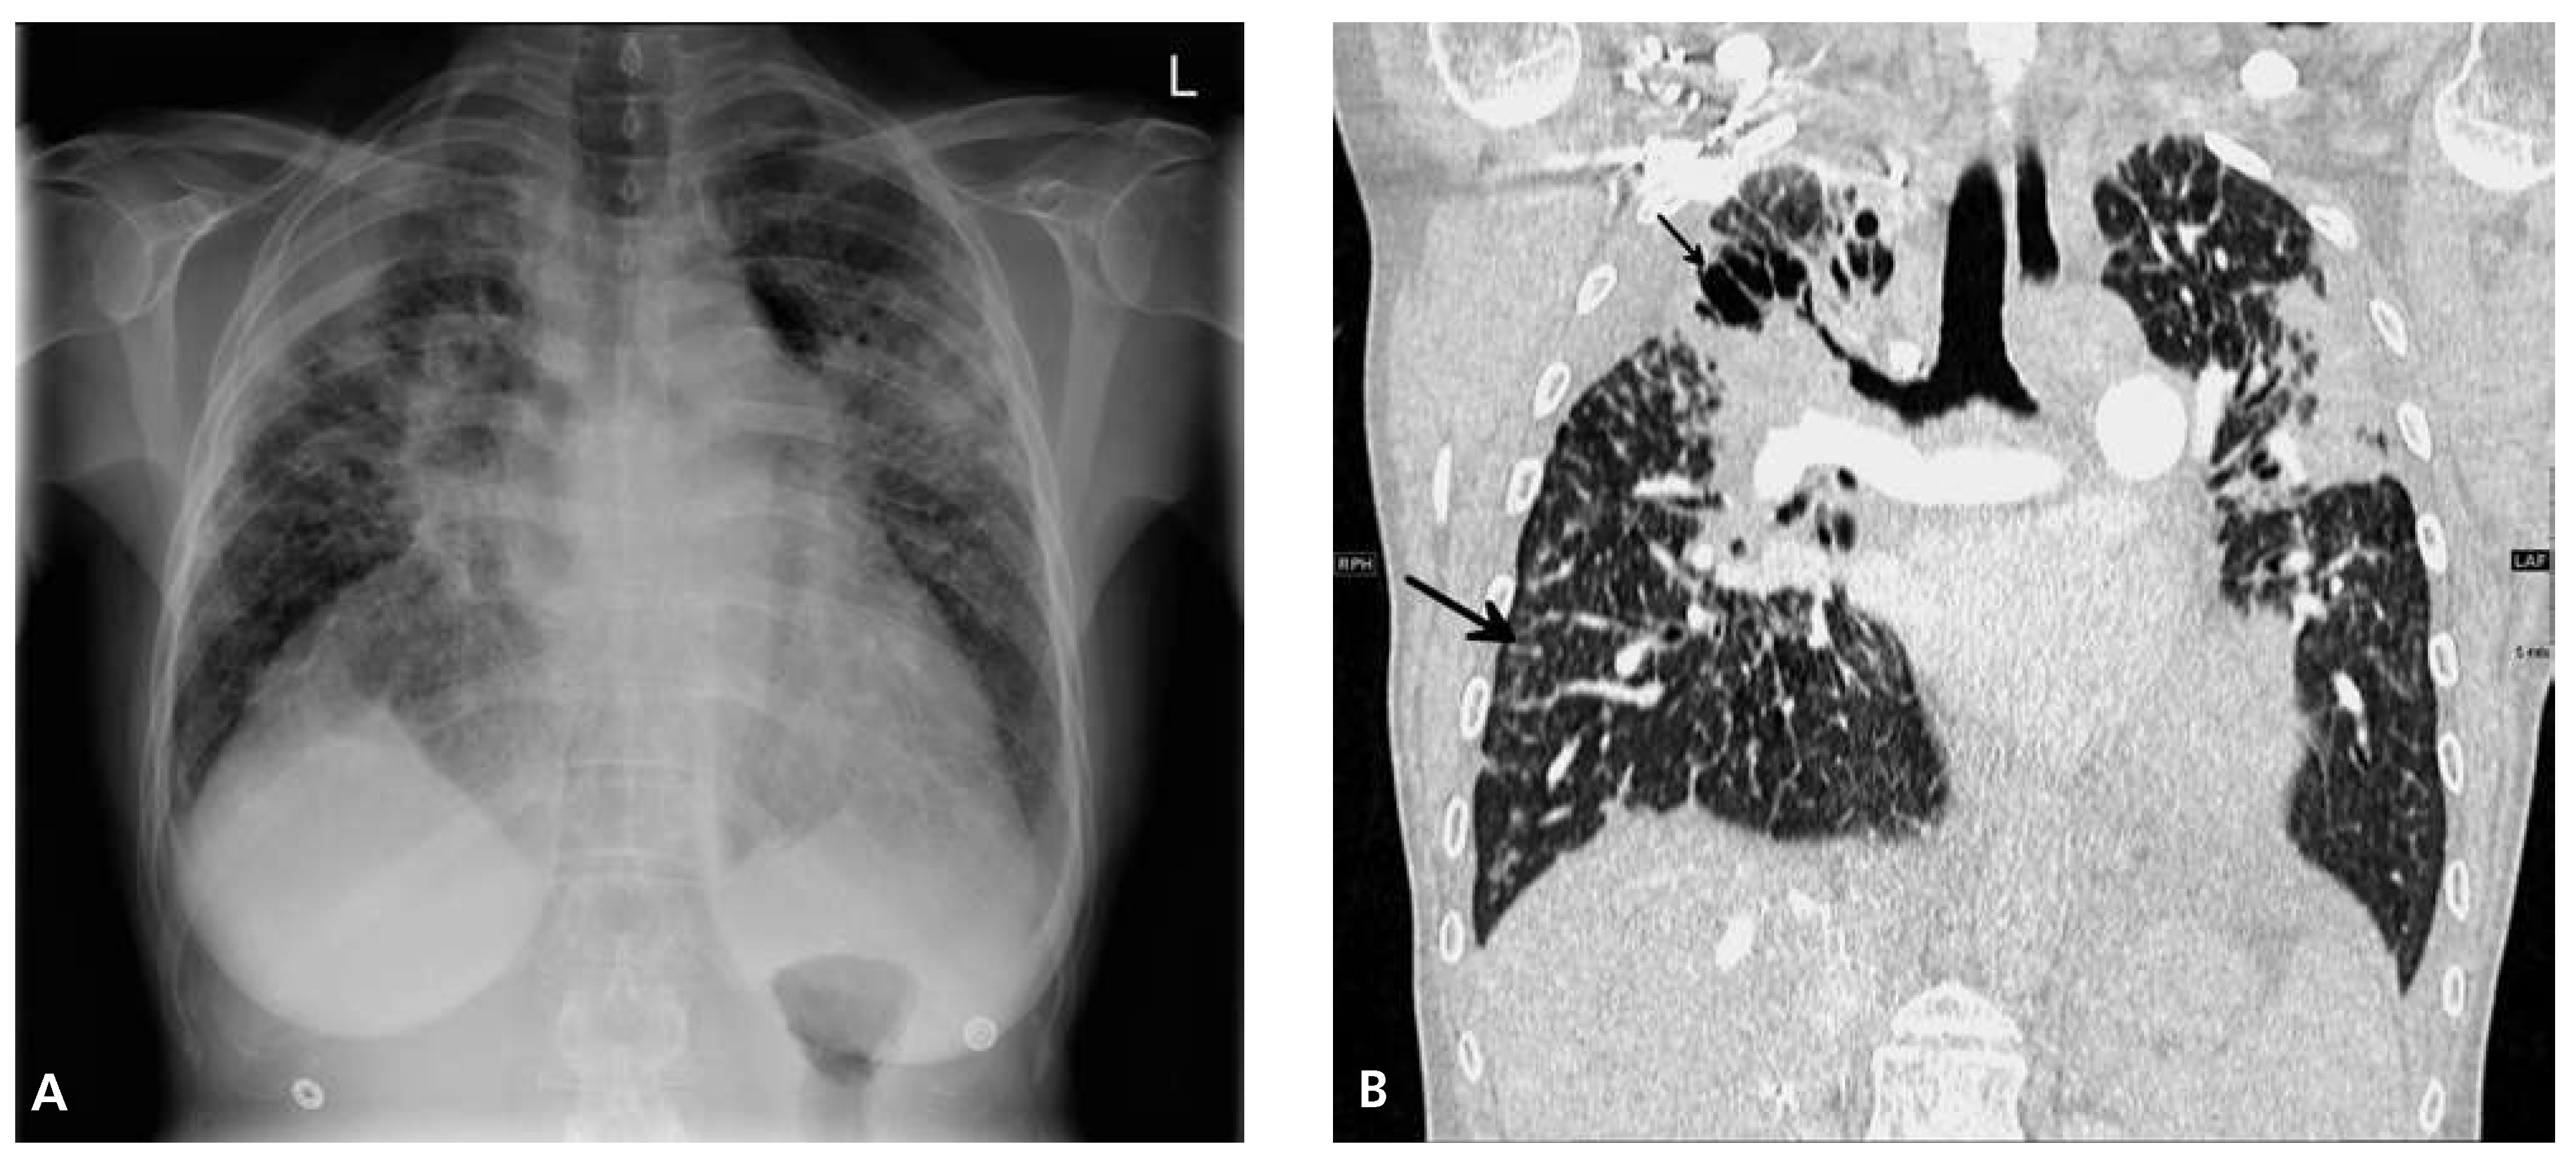

Heart Failure in a Patient with Multi-Organ Sarcoidosis